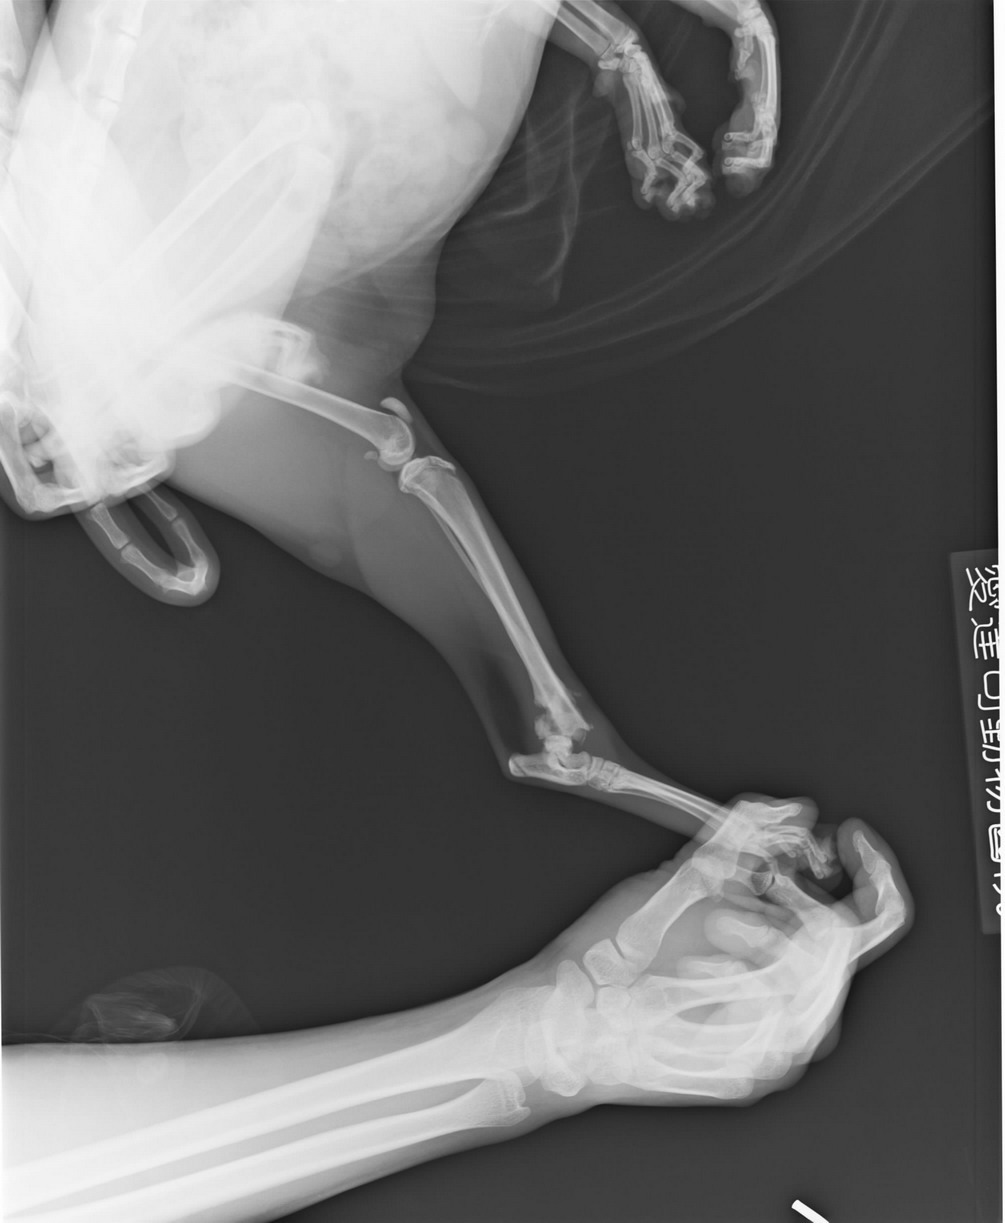

主題: 斷腳賓士喵醫療費用 申請者姓名: Jill Ringo 花色: 申請日期: 2012-04-18 14:11:42 申請者部落格: http://jilltgh002.pixnet.net/album/set/1116962 申請者臉書網址: https://www.facebook.com/update_security_info.php?wizard=1#!/profile.php?id=1358326057 所在縣市/合作醫院: 新北市/愛達司動物醫院 治療費用: 1800元 需求人數: 2人 已結案 (2012-05-17 14:36:36) 報名人員: jesi52(已付款)、jesi52(已付款)、 候補人員: 動物病情說明: 這隻賓士是在我的餵食區被人帶去剪耳後丟過來的,3/2看到她走路跛跛的,所以決定抓她去看醫生。先趕在關門前衝去誠恩~照了X光~確定她左後腳被車壓斷,當時醫生表示動骨科手術要1萬5,也可帶回家關籠讓她靜養自行修復。

2周後聽其他喵友意見再帶去愛達司再照一次X光(圖2),醫生表示斷骨處已開始修復,無需再動手術,用鋁板固定包紮後一樣帶回家關籠靜養。2周後4/3回診再照一次片子(圖4),骨頭長的還不錯就拆掉鋁板,但一樣關籠讓喵開始習慣用左腳。目前仍在我家觀察左腳復元情況。